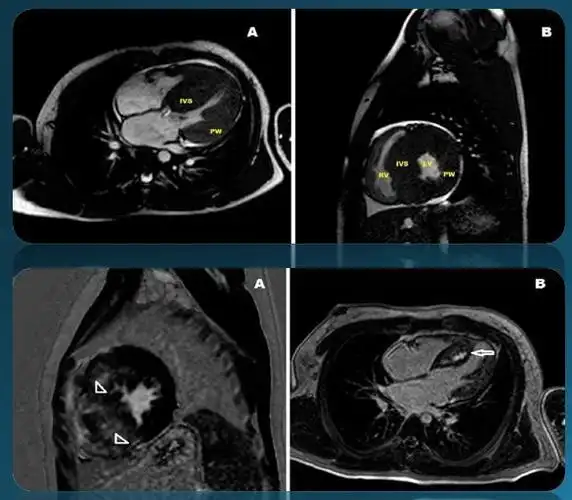

主题: 电气性和解剖性左心室肥大的临床诊断

心电图可以作为一个有用的筛选工具,显示左心室肥厚(下图),时间间隔变